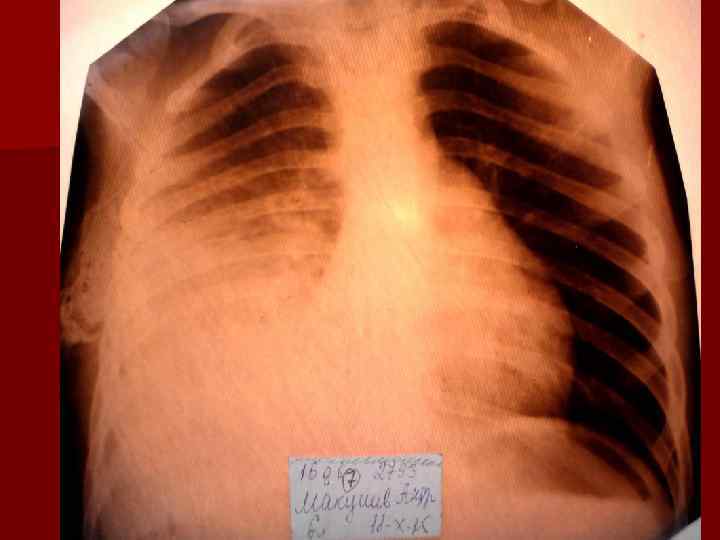

Долевая пневмония характеризуется лобарным пневмоническим инфильтратом. Крупозная ( пневмококковая) пневмония диагностируется прежде всего по клиническим данным. Крупозная пневмония сохраняет свою типичную картину пневмококковой пневмонии: острое начало с характерными клиническими данными, циклическое течение, несклонность к деструкции, гомогенной и лобарной инфильтративной тенью при рентгенологическом исследовании. Вместе с тем, широкое использование антибиотиков способствовало значительному снижению числа крупозных пневмоний у детей. Интерстициальная – редкая форма пневмоний, при которой оказывается поражен прежде всего интерстиций. Как правило, интерстициальная пневмония обусловлена вирусами, пневмоцистами, внутриклеточными микроорганизмами и грибами.

Морфологическую форму пневмонии определяют по клинико – рентгенологическим данным: выделяют очаговую, очагово – сливную, долевую ( крупозную), сегментарную и интерстициальную пневмонии. Очаговая – наиболее распространенная форма. Пневмонические очаги чаще бывают размером 1 см и более. Очагово – сливная – инфильтративные изменения в нескольких сегментах или во всей доле легкого, на фоне которых могут быть видны более плотные участки инфильтрации и/или полости деструкции. Сегментарная – в процесс вовлекается весь сегмент, который, как правило, находится в состоянии гиповентиляции, ателектаза. Морфологическая картина воспаления при очаговых и сегментарных пневмониях связана с первичным инфекционным воспалением в бронхах, что дает основание отнести эти варианты поражения легочной ткани к бронхопневмониям, нередко сопровождающихся бронхообструктивным или бронхообтурационным синдромами. В настоящее время данный тип пневмоний у детей встречается наиболее часто.